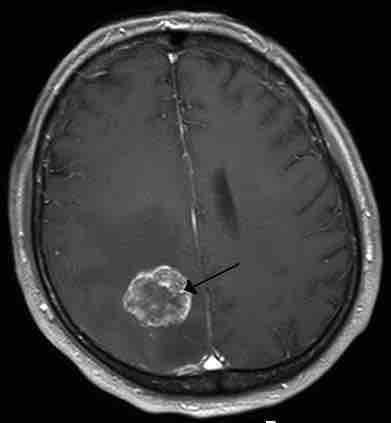

Metastasis in the Right Hemisphere

Brain metastasis in the right cerebral hemisphere from lung cancer shown on T1-weighted magnetic resonance imaging with intravenous contrast.